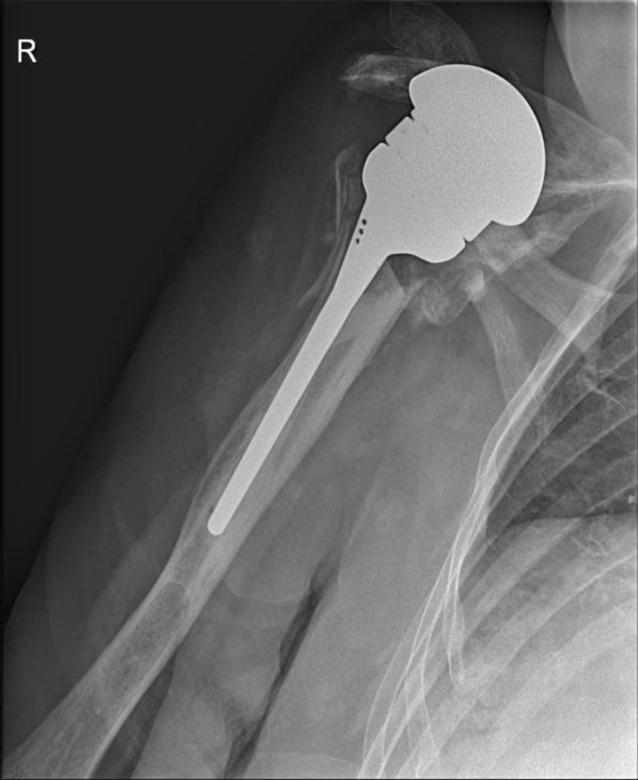

Indications for implantation of a megahead prosthesis were loosening RSA ( = 5), infection ( = 4), dislocation ( = 1) and nerve irritation ( = 1). Improvement of range of motion was observed. Anterosuperior migration of the prosthesis was noted in 2 patients. Another 2 patients were ultimately revised to RSA. Seven permanent spacers were implanted for infection, of which 2 remain in place till today. The other 5 were revised to RSA. Of the 5 patients treated with RA, 3 were revised further on to RSA, resulting in pain relief and regain of function.

植入大头假体的指征包括RSA松动(n = 5)、感染(n = 4)、脱位(n = 1)和神经刺激(n = 1)。观察到活动范围有所改善。2例患者出现假体前上移位。另外2例患者最终翻修至RSA。因感染植入了7个永久性间隔物,其中2个至今仍在位。另外5个翻修至RSA。在接受RA治疗的5例患者中,3例进一步翻修至RSA,疼痛缓解且功能恢复。